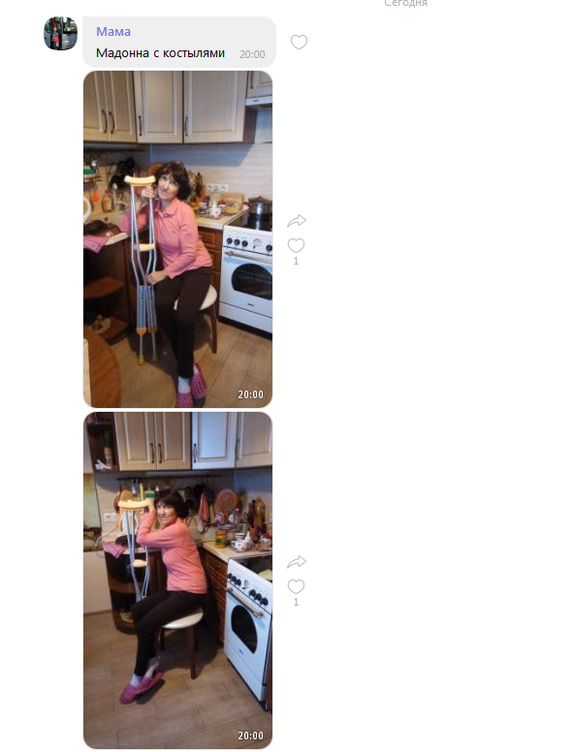

Вы приехали вовремя. Довезли мою маму до больницы, сделали операцию. Сейчас она, сами видите, уже на костылях, не смотря на такой перелом. Спасибо большое Вам! Преклоняю колени!